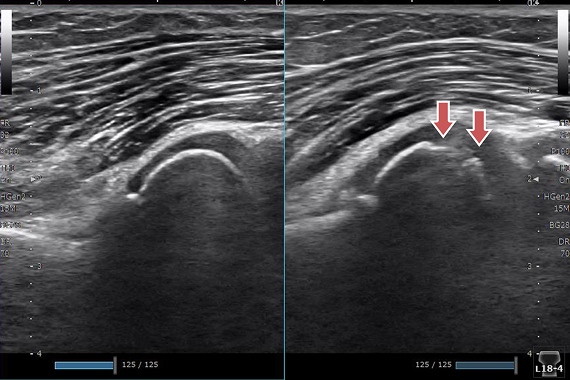

前距腓靱帯損傷

レントゲンでは評価できない靭帯損傷の有無、ゆるみの状態がわかります。